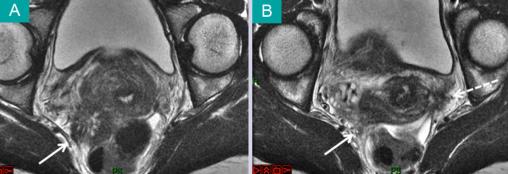

Imagerie par résonance magnétique en coupe oblique, en séquence pondérée T2. (A) Section du pelvis au niveau de l'isthme utérin. Nodule d'endométriose profonde infiltrant la fosse pararectale (flèche continue). (B) Section du pelvis au niveau paracervical. Endométriose profonde infiltrant la fosse pararectale (flèche continue). Endométriose profonde infiltrant le paramètre (flèche discontinue). Voir : Daraï É, Bazot M, Ballester M, Belghiti J. Endométriose. Rev Prat 2014;64:545-50.